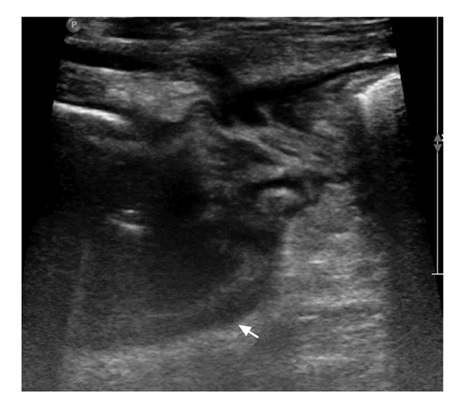

• 摘要: 肠腔狭窄是常见的克罗恩病(Crohn's disease,CD)并发症,15%的CD患者在首诊10年内可发展为肠腔狭窄。CD并发肠腔狭窄根据病理类型可分为炎症型、纤维型及混合型,炎症型为主的患者可通过药物治疗缓解症状,而纤维型为主的患者则只能通过介入或手术治疗,故采用影像学手段全面评估狭窄肠段的数目、部位、形态,并区分肠壁炎症和纤维化程度,对于临床决策十分重要。近年来,多项影像学新技术在鉴别狭窄肠壁炎症及纤维化方面取得了较大进展,有望在临床推广应用,进一步提高CD并发肠腔狭窄的诊疗。本文综述主要影像学手段包括内镜、CT、MRI、经腹超声等对肠腔狭窄的诊断价值,以期为临床提供参考。

Abstract: Intestinal stricture is one of the most common complications of Crohn's disease(CD). About 15% of CD patients can develop intestinal stricture within the first 10 years after diagnosis. CD complicated with intestinal stricture can be divided into inflammatory, fibrous and mixed types according to pathological changes. Patients with the inflammatory type can alleviate symptoms by drug treatment. In patients with the fibrous type, the affected intestinal segments can only be treated by interventional or surgical treatment. Therefore, it is very important for clinical decision-making to comprehensively evaluate the number, location and shape of narrow intestinal segments, and to distinguish the degree of inflammation and fibrosis of the intestinal wall. This article reviews the sensitivity and specificity of the main imaging methods including endoscopy, CT, MRI, and trans-abdominal ultrasound in the diagnosis of intestinal stricture. In recent years, many new imaging techniques have made great progress in differentiating inflammation and fibrosis of the narrow intestinal wall, which is expected to be widely used in clinical practice and to further improve the diagnosis and treatment of CD complicated with intestinal stricture.